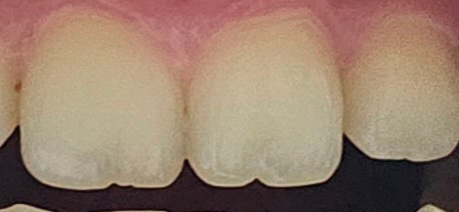

앞니가 닳았는데 많이 닳은건가요?

손톱뜯는 버릇땜에 왼쪽 앞니가 많이 닳은거같습니다 아직 중학생인데 앞니가 이렇게 닳은거면 심하게 닳은건지 궁금해요 치료가 필요한가요?

• 1번 째 사진

앞니끝부분에 다소 마모가 있습니다. 가능한손톱을 물어뜯는 행동은 피하고, 현재는 치료가 시급하지는 않습니다. 하지만 미관상 신경이 쓰이는 경우 추후 레진으로 매꾸는 치료가 가능합니다.

전체적인 모습을 봐야알 수 있지만 단순 마모보다는 원래 모양이 그럴수도 있습니다 치아 형태이상 중 쌍생치나 융합치에 대해 구글에서 관련 사진을 찾아보시기 바랍니다

사진상으로 보면 치아가 많이 마모됫거나 그렇진 않아 보입니다. 하지만 계속 손톱을 뜯으면 추후에는 문제가 생길수 있으니 습관을 고치시는게 좋습니다.

사진으로 보이는 안미는 마무라기보다 어떤 원인에 의해서 치아가 부분적으로 깨진 것으로 보입니다.

앞니로 너무 딱딱한 음식이나 젓가락 같은 거 씹으시지 마시고 조심히 사용해 준다면 더 이상 마모가 되는 것을 방지할 수 있으며 모양이 심리적으로 부담이 된다면 레진이라는 치과용 재료로 간단하게 메꿀 수 있습니다

앞니가 닳은것으로 보이지는 않습니다.

사람치아는 어릴때엔 마멜론이라는 구조가 있으며 점차 사라지는데 아직 마모되지않아 많이 남아있습니다

손톱을 물어 뜯는 습관에 의해서 나타나는 앞니 손상으로 보여집니다. 정상적인 치아의 모양은 아니며 법랑질 소실이 상당히 보입니다. 앞니의 경우에는 심미적으로 중요한 위치에 있는 치아이므로 조기에 치료하는 것이 도움이 될 수 있습니다.